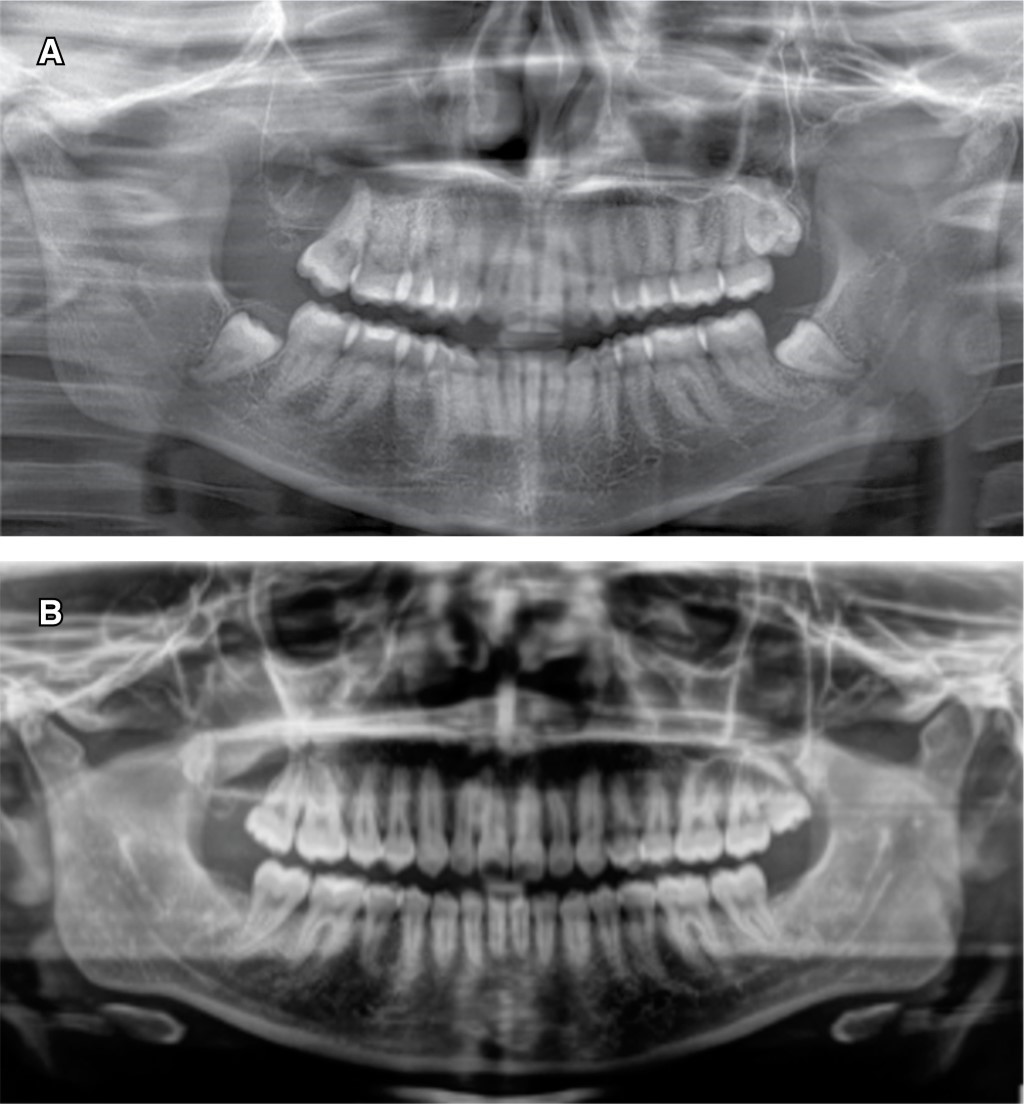

Se presentó paciente femenino de 19 años de edad a la Clínica de Cirugía Oral y Maxilofacial, de la División de Estudios de Postgrado e Investigación (DEPeI) de la UNAM, para la extracción de sus terceros molares; sin antecedentes de importancia para su tratamiento. En la ortopantomografía se observa el tercer molar superior derecho (OD 18) desplazado hasta piso de órbita ipsilateral, con una zona radiolúcida asociada a la corona del mismo, la cual ocupa todo el seno maxilar y se extiende hasta la tuberosidad del mismo lado, midiendo aproximadamente 3.3 × 5 cm, mientras que en la tomografía (cone beam) se observó la estrecha relación entre el ápice del tercer molar con el piso de órbita (Figura 1). Se inició con una punción exploratoria y se observa contenido amarillento compatible con queratina. Luego, se realizó biopsia incisional de la lesión y se extrajo el tercer molar en relación para estudio histopatológico. Se colocó drenaje utilizando una sonda Foley No. 18 y se indicó higiene estricta del mismo (Figura 2).

Se envió la muestra al Departamento de Patología de la DEPeI y se emitió el diagnóstico de queratoquiste odontogénico. Se decidió continuar con la descompresión de la cavidad quística hasta alcanzar un tamaño óptimo para la enucleación y la extracción de ésta. Se dio cita de control mensual y seguimiento radiográfico de la lesión cada cuatro meses. Ocho meses posteriores a la colocación del drenaje quístico, se observó en la ortopantomografía un cambio de densidad alrededor de la lesión, así como una mayor delimitación de la misma, por lo que se realizó la enucleación y la colocación de 5-fluorouracilo para su tratamiento (Figura 3A). Se comenzó con un abordaje a través de la pared anterior del seno maxilar, se procedió a la enucleación y curetaje del epitelio quístico, una vez retirado el tejido en su totalidad, se colocó una gasa embebida de 5-fluorouracilo (Efudix®) al 5% utilizando aproximadamente 1 g y se citó a la paciente para retiro de la gasa a las 24 horas (Figura 4). Concluidas las 24 horas se retiró el material colocado en el sitio de la enucleación y se realizó el cierre hermético de la mucosa bucal. Se envió la muestra completa para estudio histopatológico de la lesión y se corroboró el diagnóstico de queratoquiste odontogénico.

En la actualidad, la paciente sigue en control radiográfico y no se ha reportado ningún indicio de recidiva posterior a tres años, se observa el sitio de la lesión con adecuada evolución y formación de hueso en la cavidad quística (Figura 3B). Se requiere un seguimiento a largo plazo para confirmar el éxito del tratamiento, por lo cual se indicaron citas de control por al menos cinco años y control radiográfico cada tres a cuatro meses.

Figura 1

Figura 3